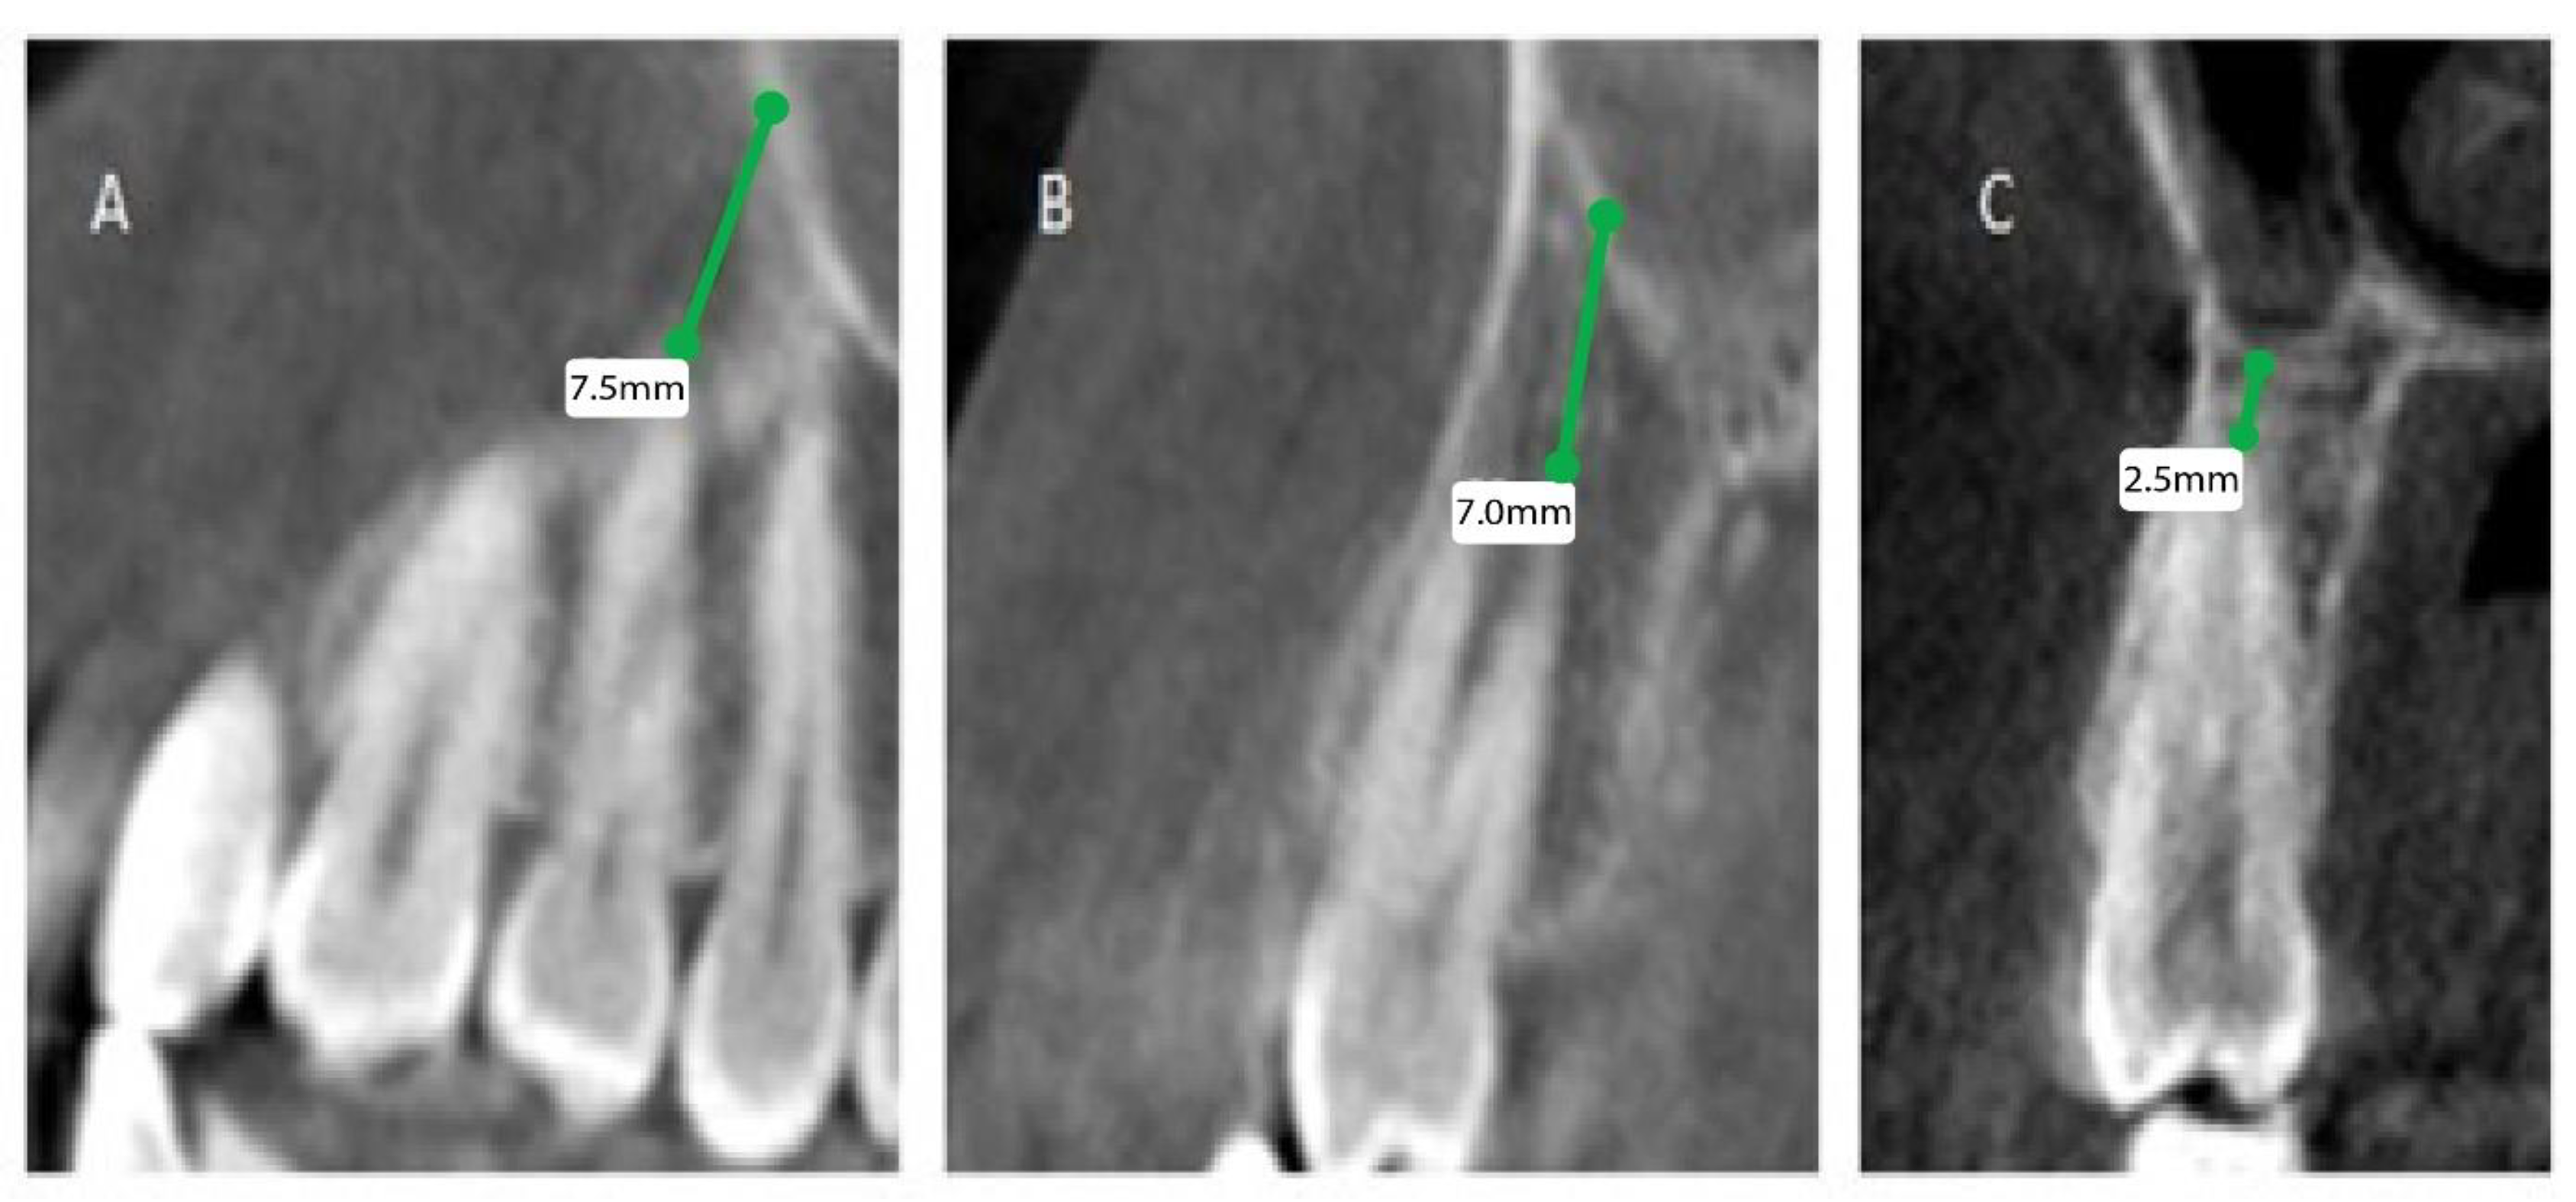

Anatomical Evaluation Of Posterior Maxillary Roots In Relation To The